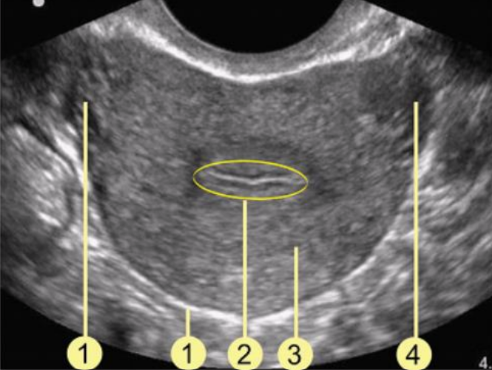

What structure is #3?

a. Bladder

b. Cervix

c. Uterus

d. Rectum

Cervix

Which uterine layer is #2?

a. Myometrium

b. Perimetrium

c. Cornua

d. Endometrium

Endometrium